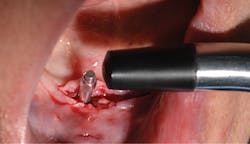

At 13 weeks, the maxillary implants were again tested, and they showed adequate stability to load (figure 12). The implant in the No. 3 position was exposed and ISQ-tested at this time. A 3 mm healing abutment was placed, and the soft tissue was allowed to heal for two weeks (figure 13) prior to placing final abutments and retrofitting the maxillary denture with locator housings.